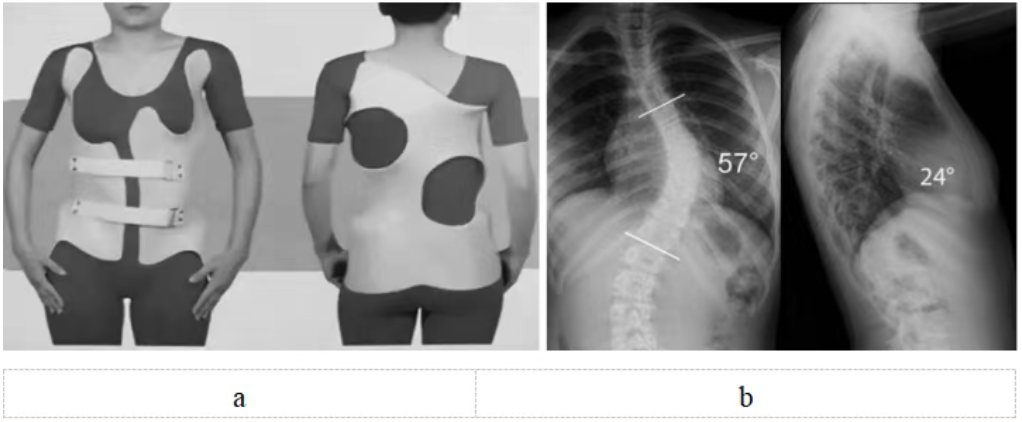

脊柱侧弯支具治疗需专业定制(图5),日用型每天佩戴20小时以上,夜用型需整晚佩戴。初期可能有不适,需1~2周适应期,要注意皮肤护理。必须坚持佩戴至骨骼发育成熟,通常需要2~3年。矫正效果取决于佩戴时长和持续性,家长要做好监督。

图5 a:特发性脊柱侧弯(中度)配戴支具正面观和背面观;b:特发性脊柱侧弯(重度)X线正侧位,需要手术治疗。注:a和b非同一患者

重度侧弯(Cobb角>40度)(图5):